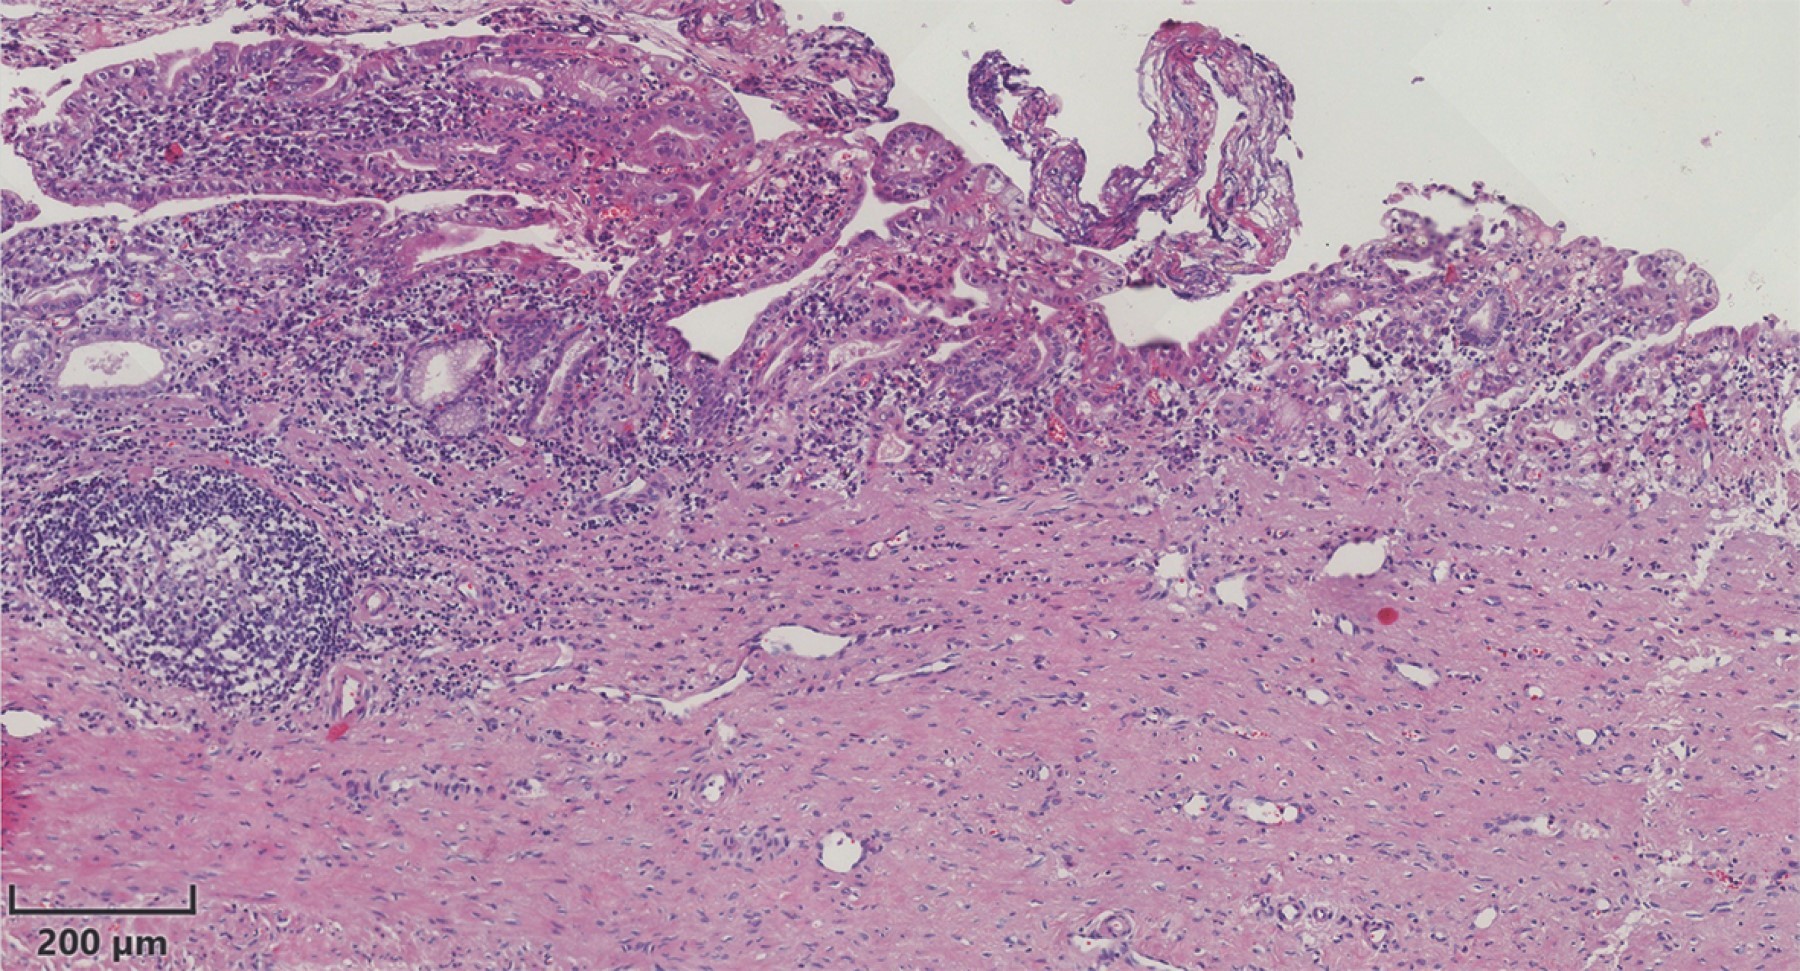

Se envía el quiste a patología para su valoración, encontrando los siguientes hallazgos: una pared del quiste compuesta por tejido fibroconectivo denso, revestido por epitelio cilíndrico simple acompañado de infiltrado inflamatorio agudo y crónico. Una lámina propia con vasodilatación e infiltrado agudo y crónico que se extiende a la pared del quiste. Hiperplasia papilar focal de la mucosa e incluso áreas de ulceración focal y una formación de un folículo linfoide secundario (Figura 6).